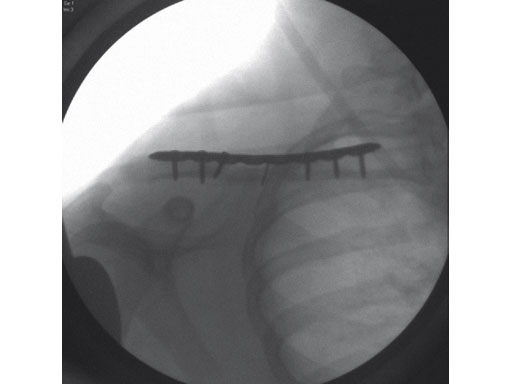

Fig 2ab Postoperative images.